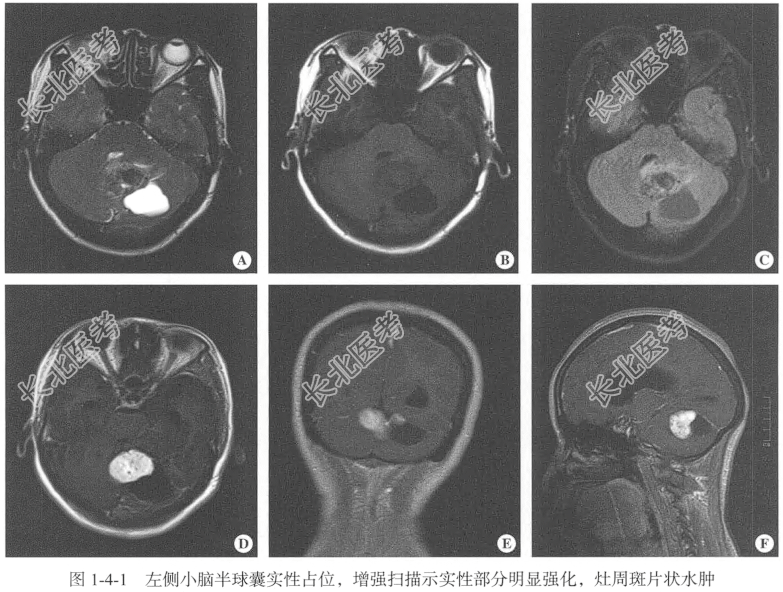

- [材料题] 【临床病史】女性,46岁。头痛伴恶心1年,加重5天。

【专科查体】患者神志清,精神可,定向定位准确,病理征阴性,脑膜刺激征阴性。

【头颅MRI检查】仰卧位,横断位扫描,包括T₁WI、T₂WI及T₂FLAIR序列,扫描范围自颅顶至小脑下缘以下,扫描层厚为5.00mm,层间隔0.50mm,矩阵512×512;辅以矢状位T₂WI序列,平扫后行横断位、冠状位及矢状位的增强扫描。

【影像图片】见图1-4-1。

【手术所见】肿瘤血供较丰富,与脑组织界线不明显,肿瘤大小约5.00cm×3.00cm,肿瘤呈灰白色,质中,肿瘤邻近扁桃体,小脑扁桃体受压向下疝入颈椎管内,第四脑室略受压,沿肿瘤与正常脑组织的边界分离肿瘤,肿瘤内界靠近中线,外侧界位于小脑半球外侧,上界位于小脑幕,分块切除肿瘤。

【病理所见】肉眼所见:(小脑)不整组织一堆,大小为6.00cm×3.20cm×2.40cm,表面呈灰白色,切面呈灰黄色,质中偏韧。镜下示肿瘤由梭形细胞组成,核呈梭形、短梭形,纤维结缔组织增生,部分区域可见血管外皮瘤样结构(图1-4-2)。免疫组化结果:GFAP(-),Vim(+),EMA(-),PR(+),CD34(+),STAT6(+),Bcl-2(+),CD99(+),Ki-67(3%+),SOX10(-),S-100(-)。

【病理诊断】结合形态学和免疫组化结果诊断为孤立性纤维瘤。